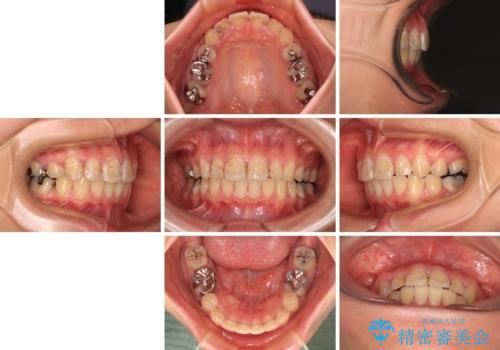

- 上の前歯の出っ歯とでこぼこの歯並びを気にして来院された患者様です。

上下顎歯列ともに前方に突出していましたが、上顎歯列がより前方位にあったため、上顎左右は第1小臼歯を、下顎左右は第二小臼歯を抜歯することとしました。

目立たないワイヤー装置にて抜歯矯正を行うこととしました。

下顎は過剰歯が埋伏しており、それが原因となってスペースが閉じなかったため、途中で抜歯して速やかに仕上げました。